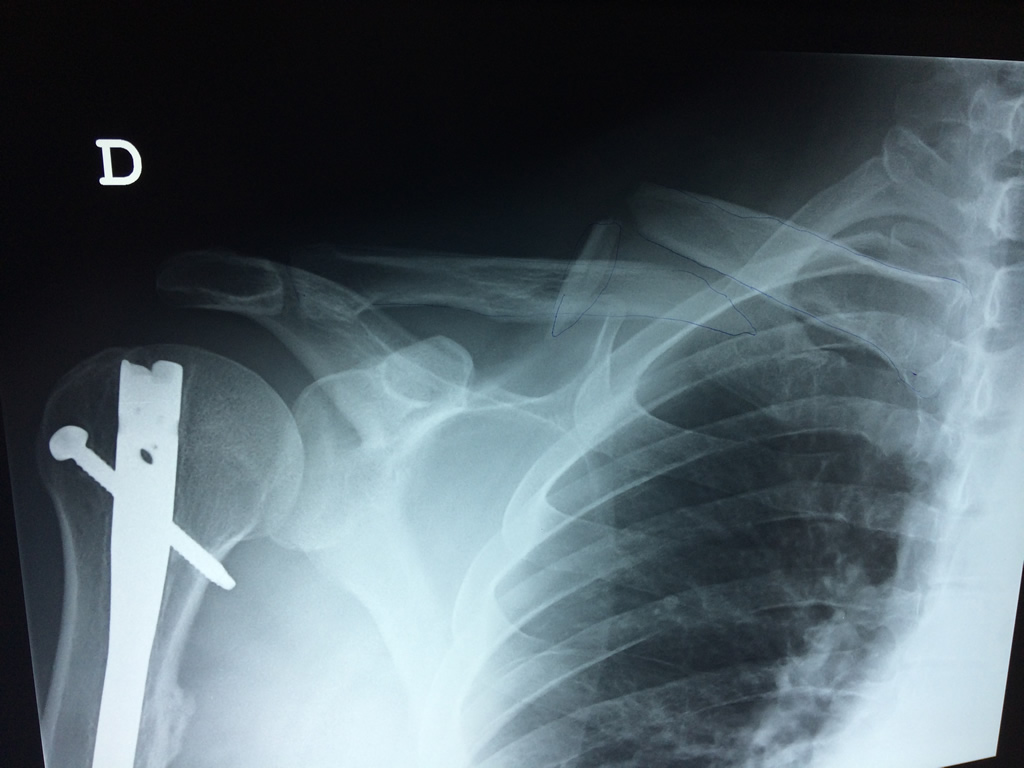

Calcaneo - Clavícula

La clavícula es un hueso largo, con forma de "S" itálica, situado en la parte anterosuperior del tórax. Junto con la escápula forman la cintura escapular. Se puede palpar por toda su longitud y se extiende del esternón al acromion de la escápula, siguiendo una dirección oblicua lateral y posterior.

Se considera el único medio de unión entre el miembro superior y el tórax. A pesar de su aspecto, similar al de un hueso largo, posee una estructura semejante a la de un hueso plano, ya que carece de epífisis y de diáfisis, lo que la harían entrar dentro de la clasificación de hueso largo. Carece de un canal medular propiamente dicho.